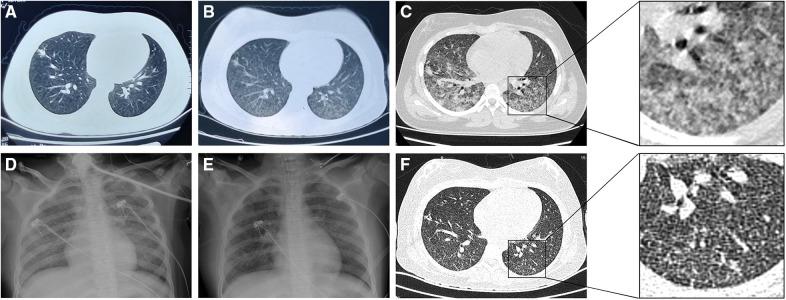

Acute respiratory distress syndrome (ARDS) is a rare complication of miliary tuberculosis, particularly in pediatric patients. Comorbidities and delayed diagnosis can worsen the prognosis of patients with miliary tuberculosis. A 12-year-old girl presented with fever for 20 days, and cough and tachypnea for 4 days. She was diagnosed with miliary tuberculosis complicated by pediatric ARDS. She had atypical clinical manifestations and imaging findings, a negative contact history, and negative results of a tuberculin skin test (TST) and T-SPOT.. Diagnostic bronchoscopy and bronchoalveolar lavage helped make the diagnosis of tuberculosis. Effective treatment was promptly initiated after confirmation of the diagnosis, and the patient's condition improved. This case illustrates that a negative contact history and laboratory results cannot rule out tuberculosis. False-negative TST and T-SPOT. results should be evaluated carefully. Bronchoscopy may be useful for identifying pathogens in patients with pneumonia of unknown etiology, and corticosteroids should be administered with caution.

急性呼吸窘迫综合征(ARDS)是粟粒性肺结核的一种罕见并发症,尤其在儿科患者中。合并症和诊断延迟会使粟粒性肺结核患者的预后恶化。一名12岁女孩出现发热20天,咳嗽和呼吸急促4天。她被诊断为粟粒性肺结核并发儿科ARDS。她有非典型的临床表现和影像学表现,接触史阴性,结核菌素皮肤试验(TST)和T-SPOT结果均为阴性。诊断性支气管镜检查和支气管肺泡灌洗有助于确诊肺结核。确诊后立即开始有效治疗,患者病情好转。该病例表明,接触史阴性和实验室结果不能排除肺结核。应仔细评估TST和T-SPOT的假阴性结果。支气管镜检查可能有助于识别病因不明的肺炎患者的病原体,使用糖皮质激素时应谨慎。